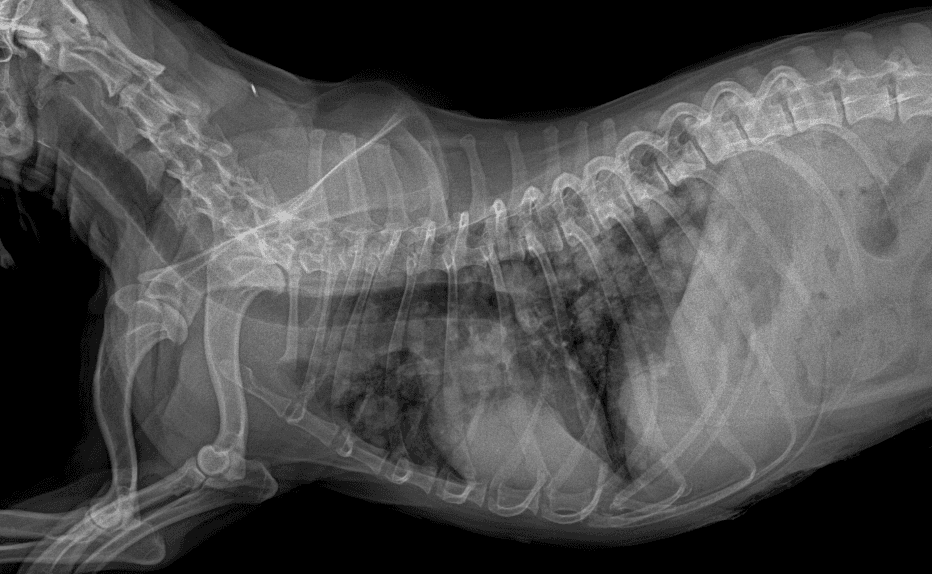

대표원장

동탄 1 신도시 최초 Aquilion CX/128 slice CT를 동물병원에 도입하였습니다. 최고 사양 CT 모델 Aquilion CX/128 slice를 활용하여 0.5 mm의 얇은 128개의 단면 영상을 신속히 획득 할 수 있어 마취 시간을 단축시킬 수 있습니다. 또한, 128 슬라이스의 고화질의 CT 영상을 통해 영상 왜곡을 최소화하고 X-ray에서는 확인하기 힘든 5 mm 이하의 미세 병변도 확인이 가능하여 정확한 진단을 할 수 있습니다. 심화 진단이 필요한 경우, 조영제 인젝터를 통한 동맥기 촬영으로 종양 유래 확인, 간 질환 진단, 심혈관계 진단이 용이합니다. 저희 동탄시티동물의료센터에서는 본원 환자뿐 아니라 1차 동물 병원과의 CT 촬영 의뢰 시스템을 통해서 원활한 협진이 가능하도록 최선을 다하고 있습니다.

0164 채널 CT 촬영을 통해서 신속하게 고화질 영상을 얻어, 종양 유래 확인 및 전이 평가, 간문맥단락증(PSS), 선천적 뼈 기형과 같은 심화된 진단을 할 수 있습니다.

64채널 검출기 시스템 128

슬라이스 이미징 능력

고속 스캔 및 높은 해상도 제공

저선량 기술 적용으로 환자 방사선 노출 감소

흉복부, 골격계 전반의 선명하고 우수한 영상을 저선량으로 촬영이 가능